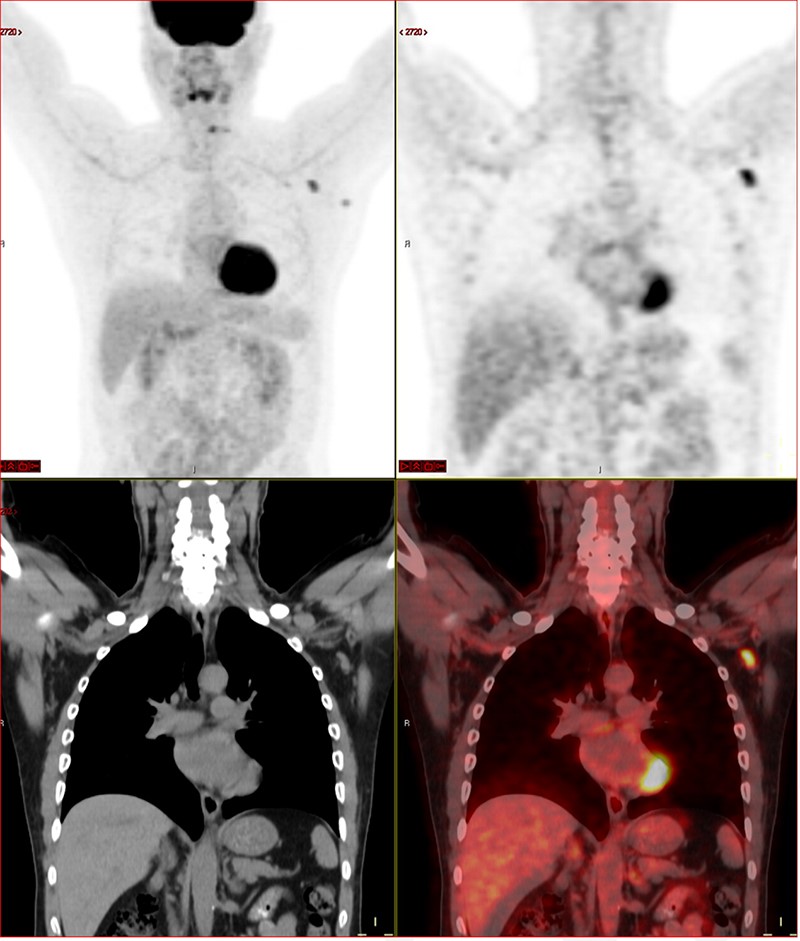

Studies including recent Radiology research have reported the presence of FDG-avid reactive axillary lymphadenopathy on PET/CT in patients who received their second mRNA-based COVID-19 vaccination dose.

A new retrospective Radiology research letter has determined that FDG uptake in axillary lymphadenopathy persisted seven to 10 weeks after the second mRNA-based COVID-19 vaccine. Pfizer and Moderna are two examples of this type of vaccine.

“Following the rapid rollout of the Pfizer-BioNTech vaccine in Israel, we almost immediately started seeing avid axillary lymph node FDG uptake in a large portion of our PET/CT patients,” Dr. Eshet said.

“The uptake values were much higher than we were used to — sometimes simulating underlying pathologies, such as breast cancer or lymphoma,” she said.

Researchers analyzed data for the presence of FDG-avid axillary lymphadenopathy on the same side of the body as the injection site at least 42 days after patients’ second COVID-19 vaccine dose. Bilateral axillary lymph node uptake was then measured by three board-certified radiologists.

“While FDG uptake noted in seasonal flu shots usually disappears within six weeks, our study found increased axillary lymph node uptake in 29% of all vaccinated patients seven to 10 weeks after receiving the second dose,” Dr. Eshet said.